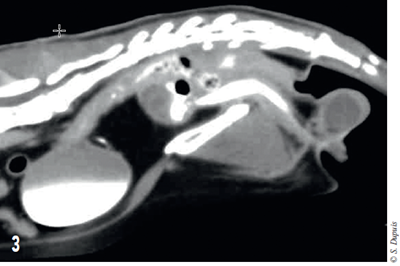

Une urétrographie de contraste positif est réalisée et montre que le produit de contraste injecté se répand dans les cavités de la masse (figure 3).

Photo 3 – Coupe sagittale tomodensitométrique de l’abdomen. Visualisation du produit de contraste injecté dans l’urètre